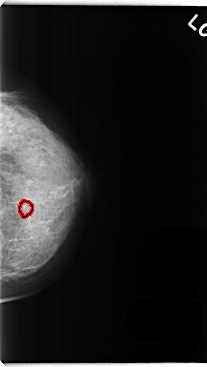

C_0257_1.LEFT_CC

FILE: C_0257_1.LEFT_CC.OVERLAY

TOTAL_ABNORMALITIES 1

ABNORMALITY 1

LESION_TYPE CALCIFICATION TYPE ROUND_AND_REGULAR DISTRIBUTION CLUSTERED

ASSESSMENT 3

SUBTLETY 5

PATHOLOGY BENIGN

TOTAL_OUTLINES 1

BOUNDARY